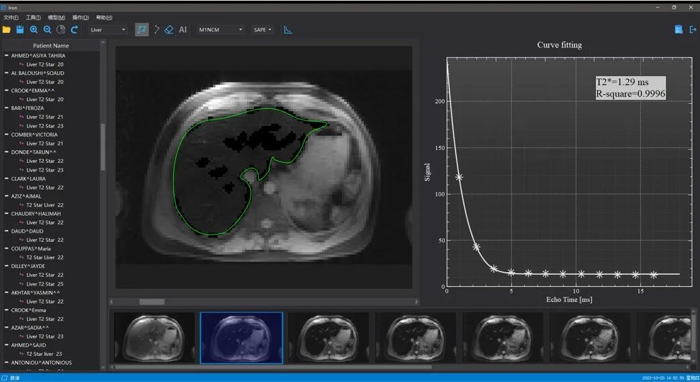

▲铁捕快软件

二是率先在国内应用核磁共振技术精准、无创定量检测地中海贫血患者心脏、肝脏铁浓度,完成5000多例地中海贫血患者脏器铁过载监测;搭建了目前国内最大规模的地中海贫血影像数据库,自主研发的人工智能辅助诊断脏器铁过载软件“铁捕快”,在国内和东盟众多医院推广应用。